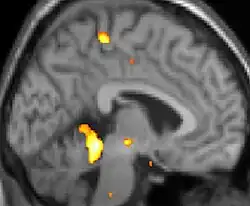

![]() | ![]() | ![]() |

| Tomografia PET mostrando áreas ativadas na dor. | ||